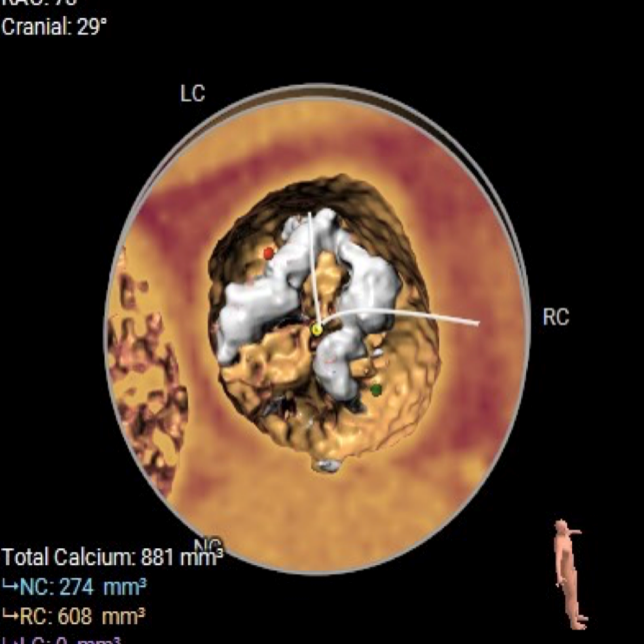

CT数据显示该患者为Type0主动脉瓣。

主动脉瓣瓣环周长97.1mm,平均周长径 30.9mm,SOV:34.8mm*47.5.3mm*42.4mm,瓣叶增厚,瓣上钙化分布不均,瓣环水平夹角66°。

钙化分布:HU850钙化积分881mm³